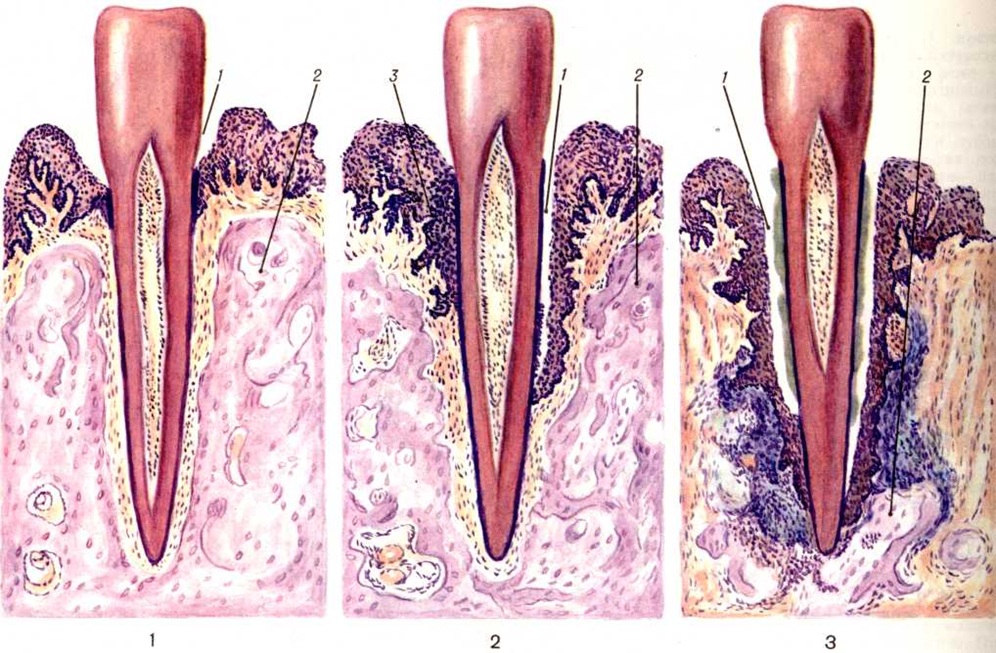

Патологическая анатомия. Пародонтоз начинается обычно с воспаления десны, протекающего как хронический катаральный гингивит (смотри полный свод знаний). В просвете десневой борозды образуются обильные напластования рыхлых базофильных масс, включающие колонии микробов и единичные эпителиальные клетки. Позже на основе богатого микробной флорой над и поддесневого плотного налёта формируется зубной камень (смотри полный свод знаний), который усугубляет патологический изменения пародонта. Хронический гингивит сопровождается воспалительной инфильтрацией десны лимфоидными, плазматическими клетками, отёком десны, активной пролиферацией, вегетацией в подлежащую соединительнотканную основу десны, а также усилением слущивания эпителиальных клеток. Состав клеточного инфильтрата (лимфоидные и плазматические клетки) характерен для реакции гиперчувствительности замедленного типа. Уже на этой стадии заболевания в костной ткани пародонта обнаруживается нерезко выраженная лакунарная резорбция кости альвеолярного отростка (цветной таблица, ст. 369, рисунок 1, 2).

Следующим этапом патологический процесса является формирование пародонтального кармана, характеризующееся разрушением эпителиального покрова в области зубодесневого соединения, вегетацией пластов эпителия в глубь периодонтальной щели. При электронной микроскопии, по данным Карсона и Сейга (R. Е. Carson, Е. S. Sayegh, 1978), отмечается исчезновение коллагеновых фибрилл периодонтальной связки, в норме вплетающихся в цемент. Содержимым пародентального кармана является некротический детрит — бесструктурные, базофильные и оксифильные массы с колониями микробов и разрушенными лейкоцитами. Наружные стенки и дно пародонтального кармана образованы грануляционной тканью, пронизанной ветвящимися пластами многослойного плоского эпителия. В костных структурах альвеолярного отростка наблюдаются выраженные резорбтивные изменения (цветной рисунок 3), начинающиеся в области верхушки альвеолярного отростка и приводящие к её полному рассасыванию. В последующем резорбтивные лакуны, содержащие остеокласты, появляются в нижележащих отделах стенок зубных альвеол, что ведёт к постепенному истончению межальвеолярных костных перегородок. Одновременно отмечается разрежение губчатой кости и в толще межальвеолярных перегородок. Процесс резорбции может протекать по типу гладкого рассасывания, лакунарной резорбции, а также как онкоз (в результате приобретения костными клетками способности к остеоклазии).

На фоне патологический изменений в пародонте и по мере углубления пародонтальных карманов в прилежащих к ним участках периодонта наблюдается прогрессирование хронический воспалительного процесса. Его морфологический проявлениями являются образование густых лимфомакрофагальных инфильтратов с примесью плазматических клеток, формирование полей грануляционной ткани, а при обострении патологический процесса — солитарных, и в некоторых случаях — множественных абсцессов. При прогрессировании Пародонтоз пародонтальные карманы и реактивный по своей природе погружной рост пластов многослойного плоского эпителия достигают верхушек корней зубов, периодонтальная связка полностью разрушается. Дальнейшая резорбция костной ткани альвеолярного отростка приводит к полному рассасыванию межальвеолярных и межкорневых костных перегородок (цветной рисунок 3). При Пародонтоз в патологический процесс довольно рано вовлекаются ткани зуба: начинается резорбция цемента, что приводит к образованию глубоких цементных и цементно-дентинных ниш. Параллельно может наблюдаться процесс новообразования цемента. В случае преобладания этого процесса развивается гиперцементоз. В пульпе зубов при Пародонтоз обнаруживают выраженные в различной степени дистрофические изменения, приводящие к сетчатой её атрофии, а также к образованию в пульпе единичных и множественных петрификатов и дентиклей. Нередко при Пародонтоз отмечается развитие ретроградного пульпита, который может закончиться гибелью пульпы.

Пародонтоз может протекать с преимущественным развитием в околозубных тканях дистрофических изменений с характерной атрофией костных трабекул губчатого вещества, выраженным очаговым остеосклерозом, чередующимся с очаговым остеопорозом (рисунок 1). Патологический изменения в костной ткани сочетаются с выраженными изменениями её кровеносных сосудов: гиперплазией внутренней оболочки, склерозом и гиалинозом средней оболочки, резким сужением или полной облитерацией просвета сосудов (рисунок 2). В соединительнотканной основе десны также отмечаются выраженные изменения сосудов, проявляющиеся пролиферацией эндотелия, образованием пристеночных тромбов, иногда развитием картины васкулита; на этом фоне довольно часто наблюдается набухание коллагеновых волокон, их фрагментация и даже лизис. В целом состояние десны характеризуется развитием в ней вялотекущего воспалительного процесса, в соединительнотканной строме десны обнаруживают инфильтраты из плазматических и лимфоидных клеток, локализующиеся преимущественно в области десневой борозды.